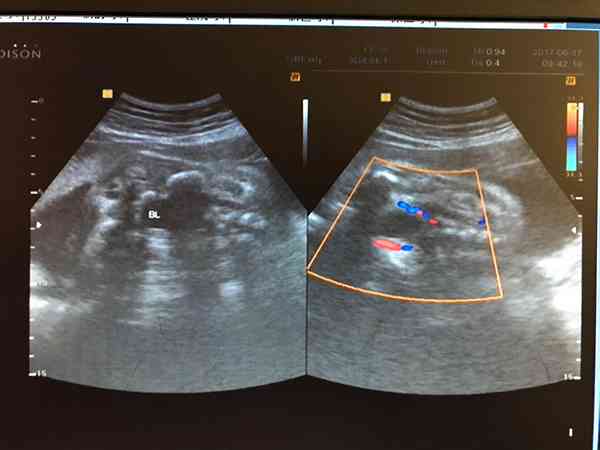

因为目前孕周已经很大了,孕期无法做更多检查确诊了。建议生后给胎儿做腹部超声,详细评估囊肿的来源和性质,遵循儿科的意见决定下一步处理。胎儿超声显示是膀胱上方的囊肿,跟膀胱应该是分开的。而这个囊肿有可能是:胎儿的腹腔囊肿,通常最常见的是卵巢囊肿(前提是女性胎儿),可以巨大;其次是肠囊肿,其超声特征为单个囊肿,很少巨大;肠系膜淋巴囊肿,超声特征为,多个大小不等的囊肿;还有如囊性畸胎瘤、肾囊肿、输尿管囊肿...